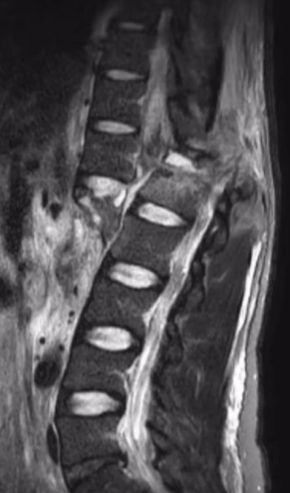

A moto foi direto nas minhas costas, causando a fratura da vértebra lombar L1.

No dia 11/12, passei por uma cirurgia de descompressão medular e estabilização da coluna, na tentativa de minimizar os danos causados pelo acidente.